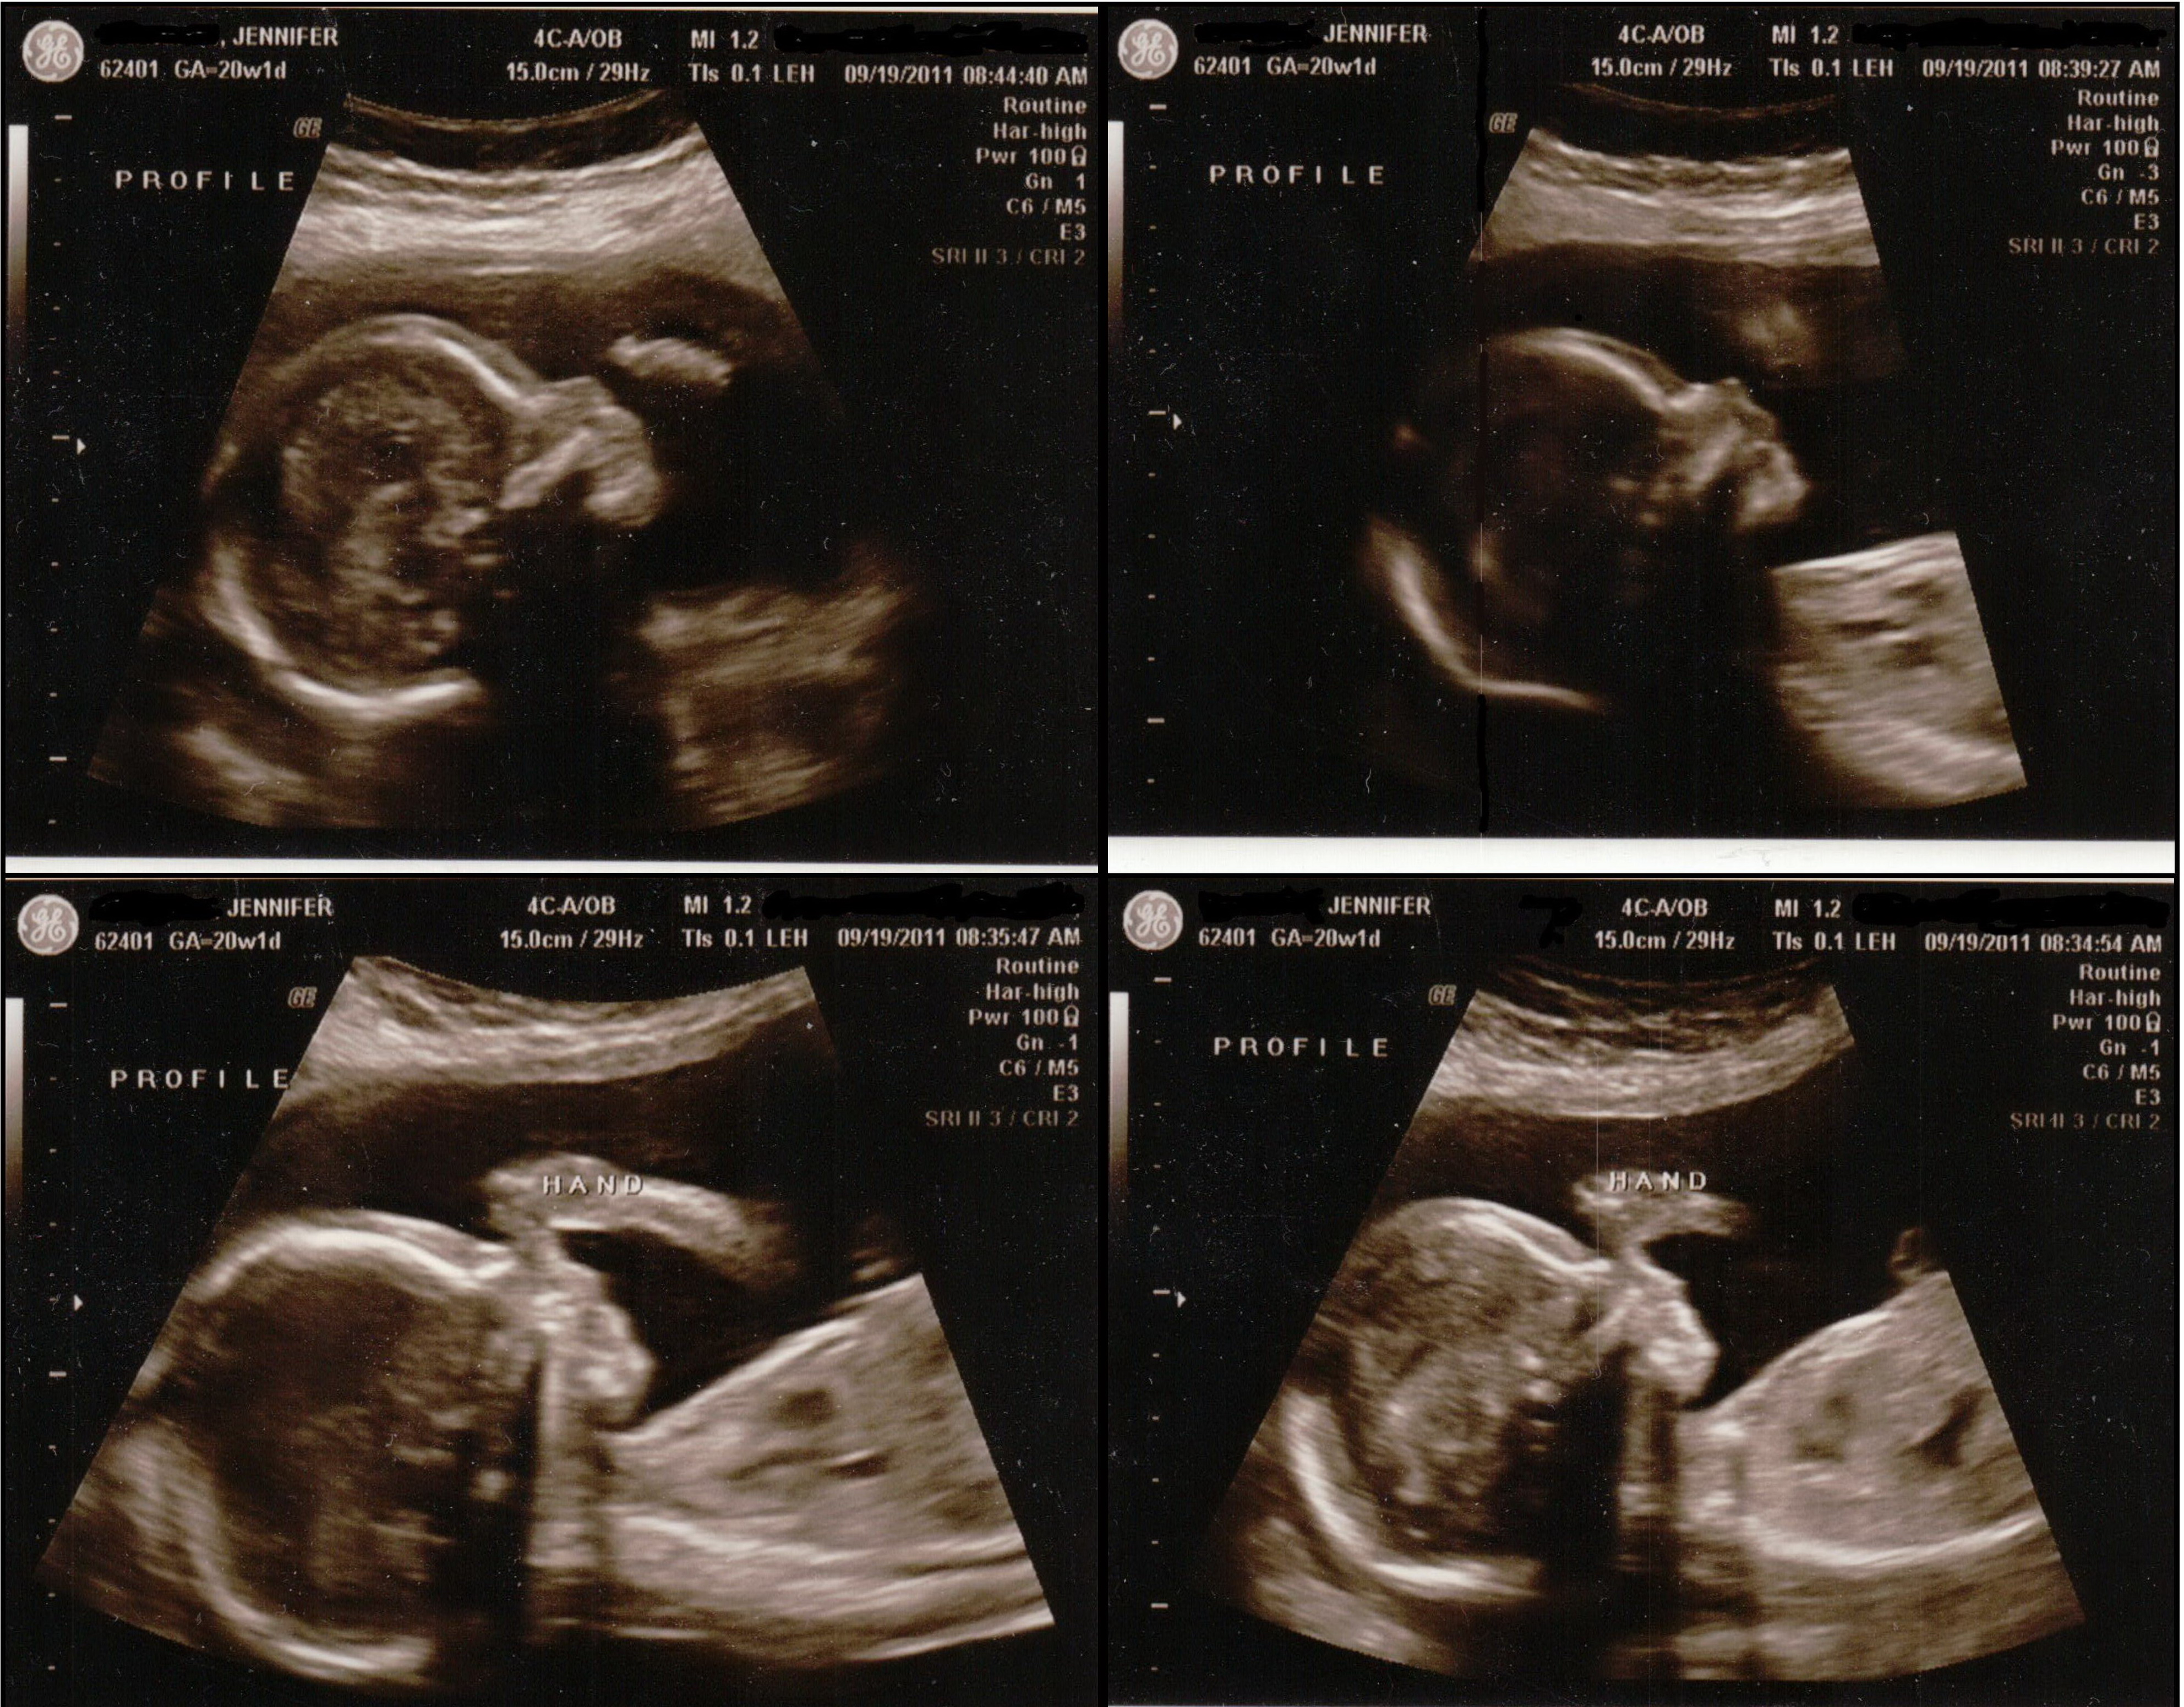

This morning I had my 20 week ultrasound. There’s no doubt about it…there’s definitely a tiny little man in there! 🙂 Today he weighed 13 ounces and his heart rate was 145. Everything looked good, he’s perfect!